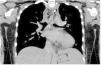

Paciente mujer de 17 años con antecedentes de meningoencefalitis en la infancia sin secuelas, que consultó por un cuadro clínico de una semana de evolución consistente en dolor cervical, odinofagia y fiebre de hasta 39°C. En la exploración física las constantes fueron estables, presentando dolor cervical a la movilización. En la analítica presentó elevación de reactantes de fase aguda. Se realizó una TAC cervical y torácica en la que se observó una gran colección cervical con abundantes burbujas de gas en su interior (figs. 1-3, asteriscos), con extensión hacia el mediastino posterior a través del espacio peligroso retrofaríngeo, hallazgos compatibles con fascitis necrosante y mediastinitis posterior. En las muestras quirúrgicas se cultivó Streptococcus dysgalactiae y S. intermedius. La paciente evolucionó favorablemente con tratamiento antibiótico y drenaje quirúrgico de la colección.